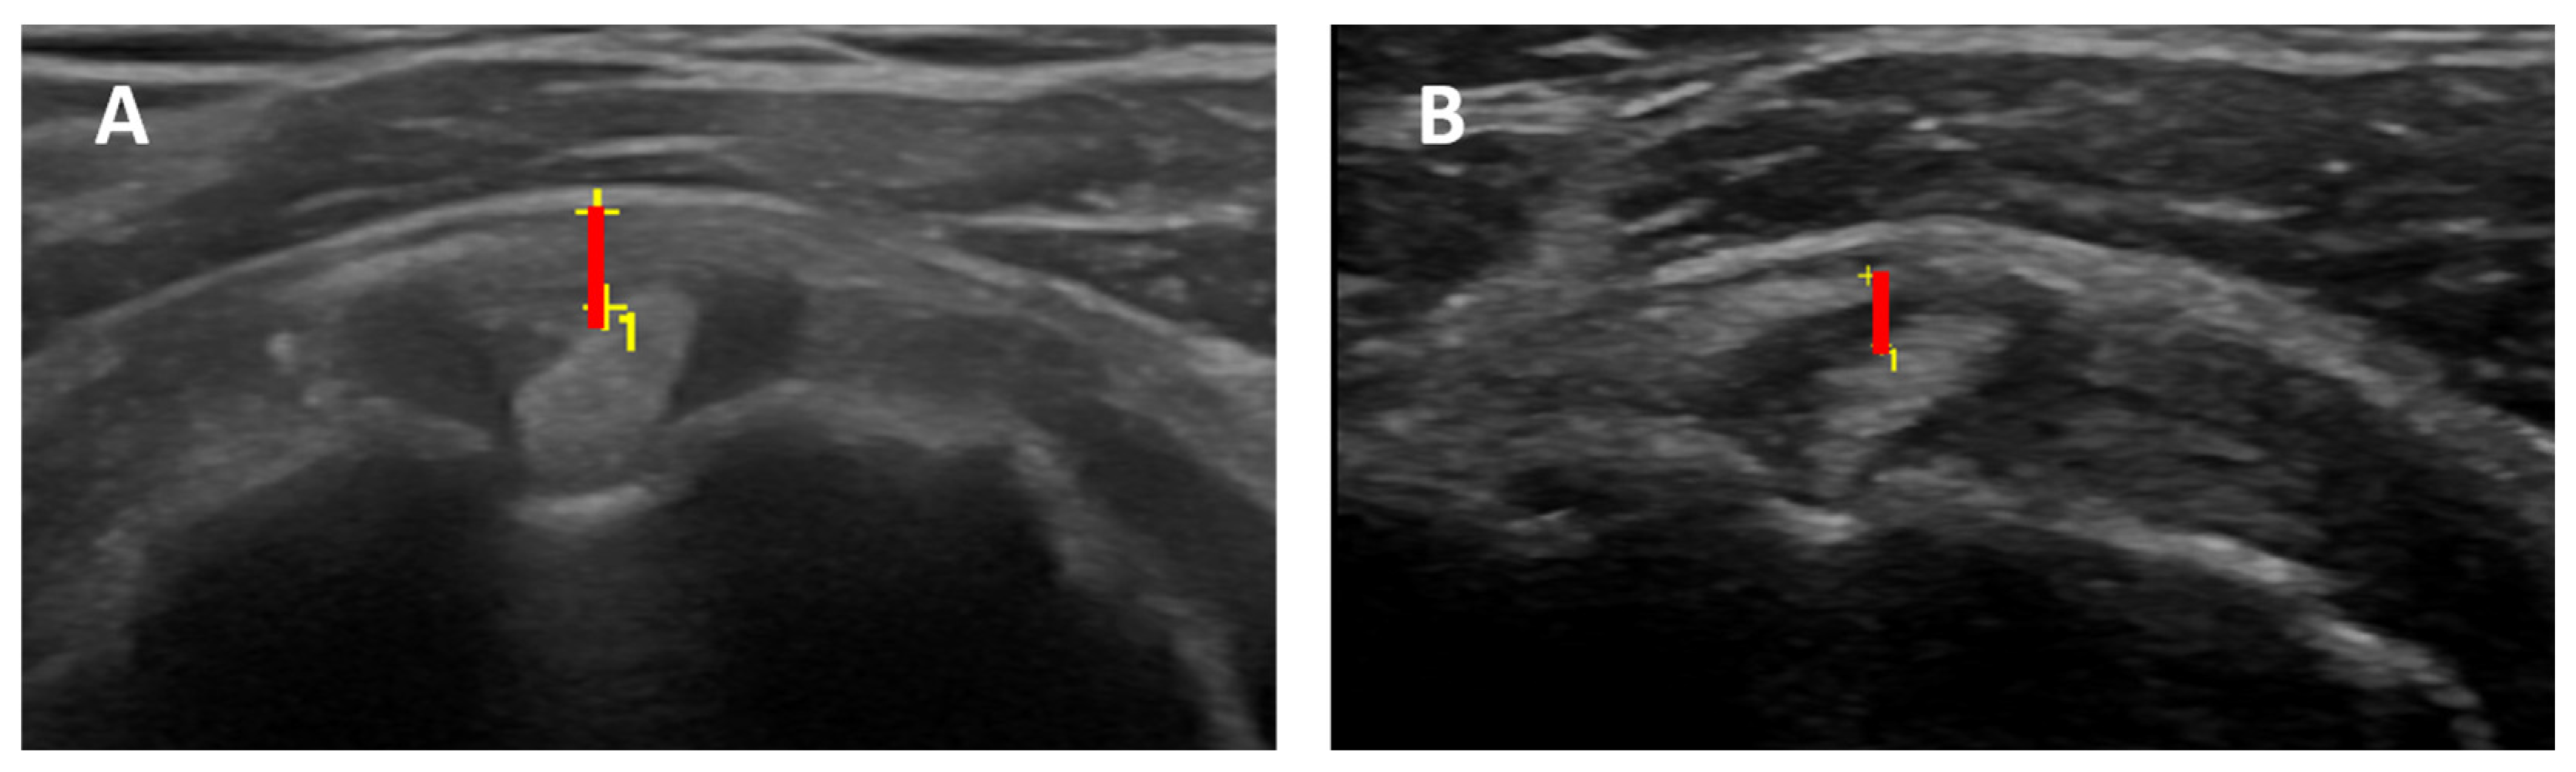

- Axillary pouch (AP) maximum thickness: evaluated in the supine or sitting position with the probe placed longitudinally on the mid-axillary line along the neck of the humerus;

- Rotator interval (RI) maximum thickness: evaluated in the sitting position with the arm in a neutral position, elbow flexed, and hand palm on the knee. RI thickness was evaluated in a scan that included LHBT, supraspinatus, and subscapularis tendons by measuring the distance between LHBT outer contour and peri bursal fat;

3.3. Axillary Pouch (AP) Thickness

3.4. Rotator Interval (RI) Thickness and Effusion within the LHBT Sheath